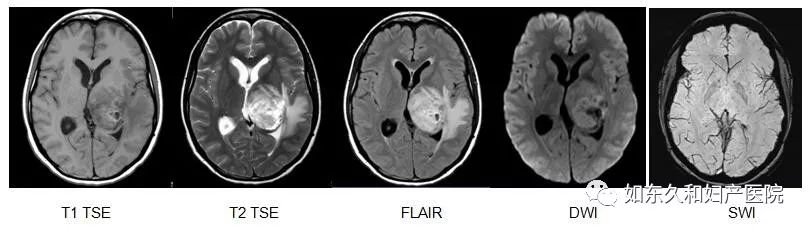

神经系统成像

MR检查具有无辐射、高软组织对比度,多层面,多参数等优势,尤其适用于神经系统检查,适应症有:脑肿瘤、血管性疾病、脑外伤、感染性疾病、脱髓鞘及变性疾病、先天畸形、代谢性疾病等。